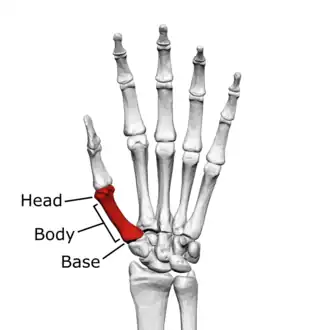

First metacarpal of the left hand (shown in red). Palmar view.

The first metacarpal bone or the metacarpal bone of the thumb is the first bone proximal to the thumb. It is connected to the trapezium of the carpus at the first carpometacarpal joint and to the proximal thumb phalanx at the first metacarpophalangeal joint.

The first metacarpal bone is short and thick with a shaft thicker and broader than those of the other metacarpal bones. Its narrow shaft connects its widened base and rounded head; the former consisting of a thick cortical bone surrounding the open medullary canal; the latter two consisting of cancellous bone surrounded by a thin cortical shell. [1]

The head is less rounded and less spherical than those of the other metacarpals, making it better suited for a hinge-like articulation.

The distal articular surface is quadrilateral, wide, and flat; thicker and broader transversely and extends much further palmarly than dorsally. On the palmar aspect of the articular surface there is a pair of eminences or tubercles which articulate with the radial and ulnar sesamoid bones of the thumb metacarpophalangeal joint; the lateral eminence is larger than the medial.

The body or shaft is thick and broad — averaging 6 to 11 millimetres (0.24 to 0.43 in). On its dorsal side, the shaft is flat and wide, while the anteroposterior side is less pronounced; usually resulting in an oval-triangular cross-section.

The dorsal surface of the shaft is weakly convex longitudinally, while its palmar, radial, and ulnar surfaces tend to be concave. The palmar and medial surface exhibits a blunt ridge which separates a larger lateral part – the insertion of the opponens pollicis muscle – and a smaller medial part – the origin of the lateral head of the first dorsal interosseous muscle.

The base is significantly different from the bases of the other metacarpals. It is trumpet-shaped and ends in a saddle-shaped articular surface matching that of the trapezial articular surface. The configuration of the thumb carpometacarpal joint plays an important role in the mechanism of opposition. The articular surface is delimited by a thick, crest-like ridge extending around its circumference.

On the palmar and lateral side of the base is the insertion of the tendon of the abductor pollicis longus muscle, usually featuring a small tubercle. The origin of the first dorsal interosseous muscle is on the ulnar aspect of the base, and can sometimes extend onto the shaft. In contrast to the other metacarpals, the first metacarpal has no articular facets on the sides of its base (for intermetacarpal articulations) because it articulates exclusively with the trapezium.